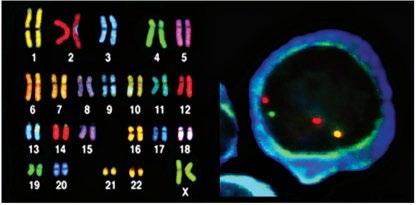

Testing To Determine A Diagnosis of Myeloma: Bone Marrow

Bone marrow biopsy & aspirate

• Bone marrow plasma cells (%)

• Congo Red staining if concern for AL-Amyloid

Bone marrow genetics

• Cytogenetics

• Fluorescence in situ hybridization (FISH)

• Next generation sequencing (NGS)

Photo

Staging and Risk Stratification

High Risk FISH Results

Fluorescence in situ hybridization (FISH) and Chromosomal abnormalities

Testing For Myeloma: Bone Marrow

High Risk FISH Results* Deletions Translocations Gain

of people with NDMM

This Photo by Unknown Author is licensed under CC BY-SA